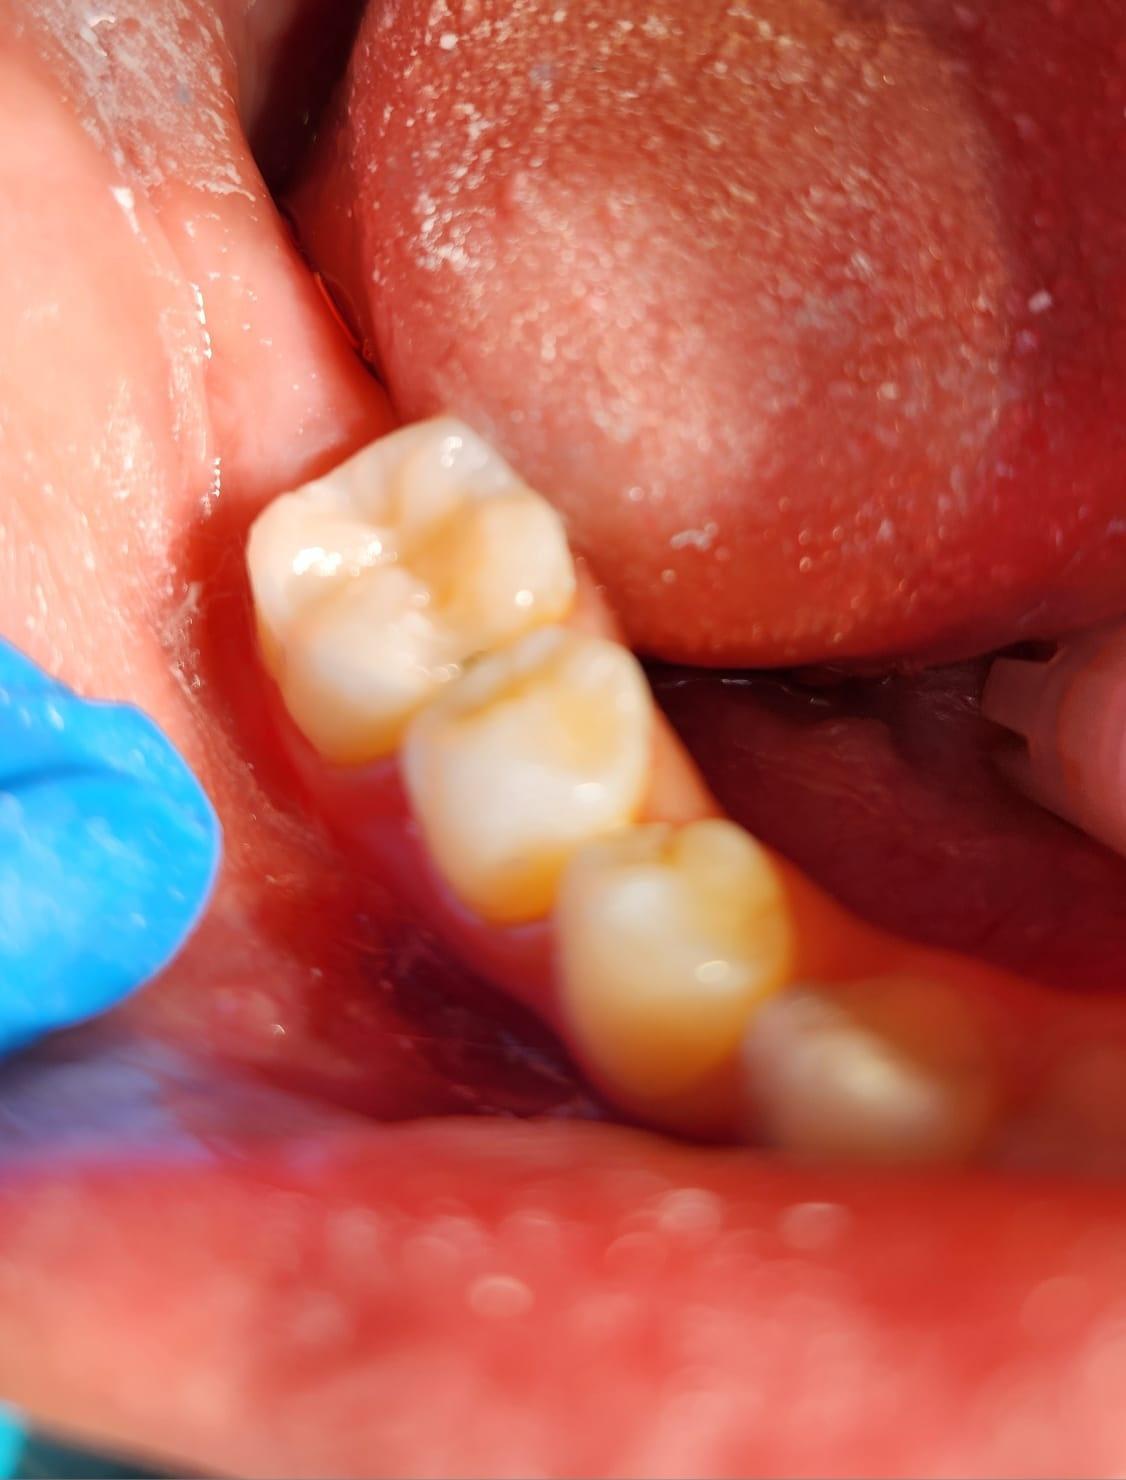

Clinica LUY ESTHETIC ART defineste parodontoza ca fiind rezultatul direct al placii dentare, care se depune pe suprafata dintilor, dar si in apropiere de marginea gingivala. Aceasta boala duce la pierderea dintilor, chiar daca ei sunt aparent sanatosi si nu prezinta carii. Edentatiile, afecteaza vorbirea, aspectul, dar si capacitatea de a mesteca.

– retractii gingivale cu expunerea radacinilor dentare;